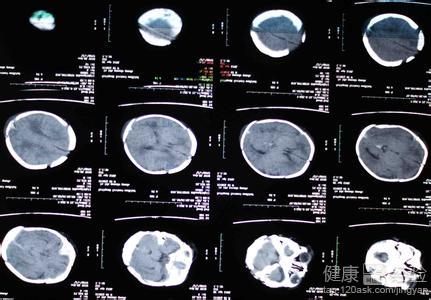

2如果想要明確的知道新生兒的大腦是否收到損害,可以帶孩子去醫院做一個腦補的B超或者腦部的CT,通過儀器檢查可以明確的了解新生兒大腦的受損情況,另外,腦電圖和腦電功率譜檢查,也可以做出明確判斷。

父母平時一定要觀察寶寶的動向,及時發現及時治療。並且定期到醫院做腦CT檢查,查看大腦細胞的恢復情況,並且做智力檢測,看看寶寶的智力是否符合正常的值范圍。平時要鍛煉寶寶的智力開發,多玩積木和寶寶做親子游戲。